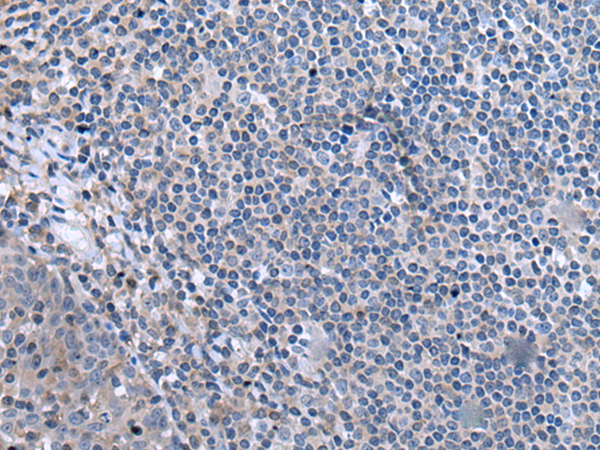

分类: 科研抗体货号: P00243别名: M33; CDCA6; SRXY5应用: WB,IHC反应种属: Human